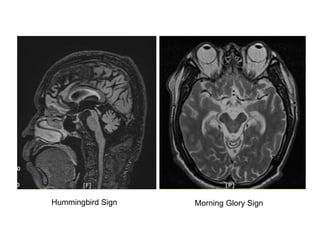

Hummingbird Sign Morning Glory Sign

• Symmetrical parkinsonism, usually without

tremor

• Prominent neck dystoniaretrocollis

• Markedly reduced blink rate

• Apraxia of eyelid opening

• Slowed vertical saccades progressing to vertical

supranuclear gaze palsy

• Postural instability (falls backward)

• Dementia

• Dysarthria & dysphagia

• Poor Levodopa response

PSP : Clinical Features